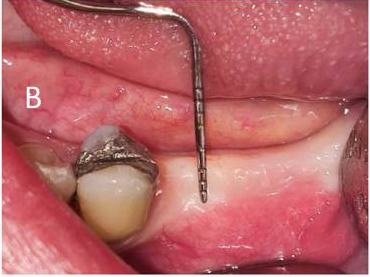

(A) Soft tissue thickness measurement (B) Keratinized gingiva measurement (C) Implant placement (D) Three months after implant placement and healing abutment closure